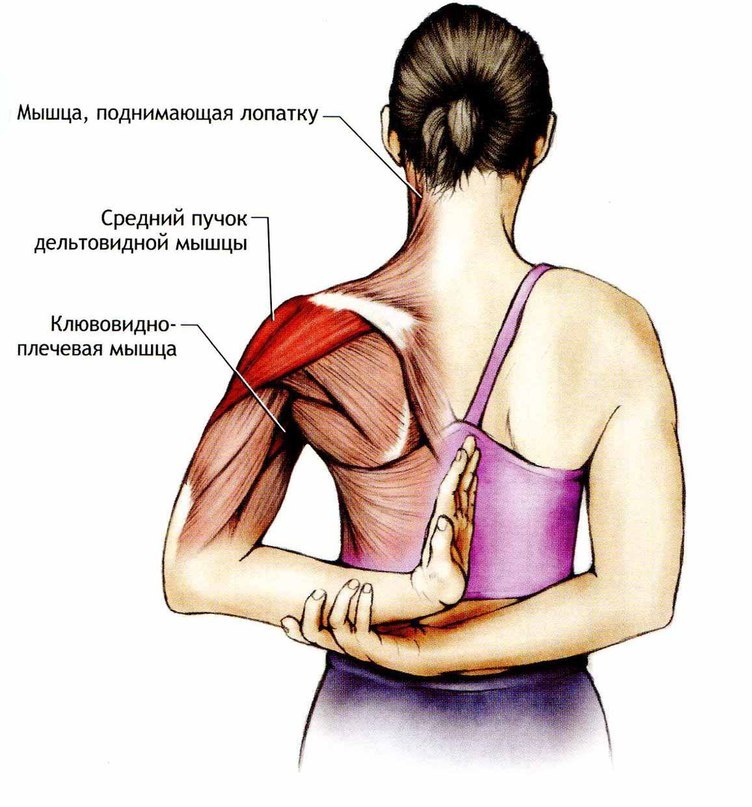

Фотографии поддельтовидной мышцы плечевого сустава